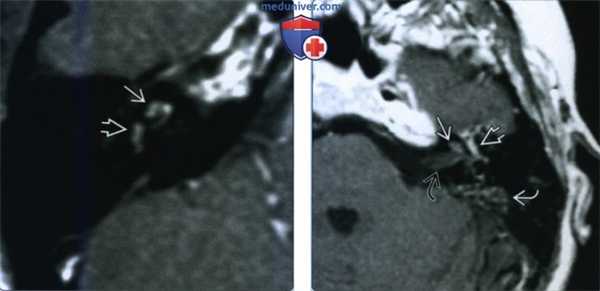

(Слева) При аксиальной МРТ Т1 ВИ С+ у пациента с внезапно возникшим головокружением и тугоухостью на фоне вирусного лабиринтита определяется патологическое контрастное усиление завитков улитки и преддверия.

(Справа) При аксиальной МРТ Т1 ВИ С+ определяется контрастирование улитки и внутреннего слухового канала у пациента с двухсторонним отомастоидитом, оталгией, параличом ЧН VII и тугоухостью. Барабанный сегмент ЧН VII в этом примере тимпаногенного лабиринтита также утолщен и накапливает контраст.